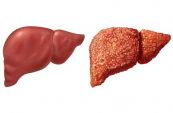

Bệnh gan xảy ra sẽ làm tổn thương các mô tế bào của cơ quan. Nếu bạn không sớm có biện pháp can thiệp, tình trạng thương tổn tế bào gan rất dễ để lại sẹo (xơ gan), từ đó dẫn đến suy gan và gây đe dọa đến tính mạng của người bệnh. Bài viết dưới đây sẽ nói rõ hơn về triệu chứng, nguyên nhân và cách điều trị của bệnh, mời các bạn tham khảo.